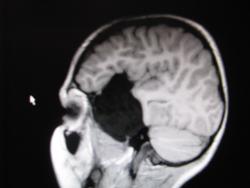

Крупная арахноидальная киста правой височной области.

Согласна, арахноидальная киста.

да, до этого мальчик жалоб не предъявлял. наверное киста увеличилась, масс-эффект на прилежащие струкутры усилился , появилась клиника.

Да, это врожденная арахноидальная киста.